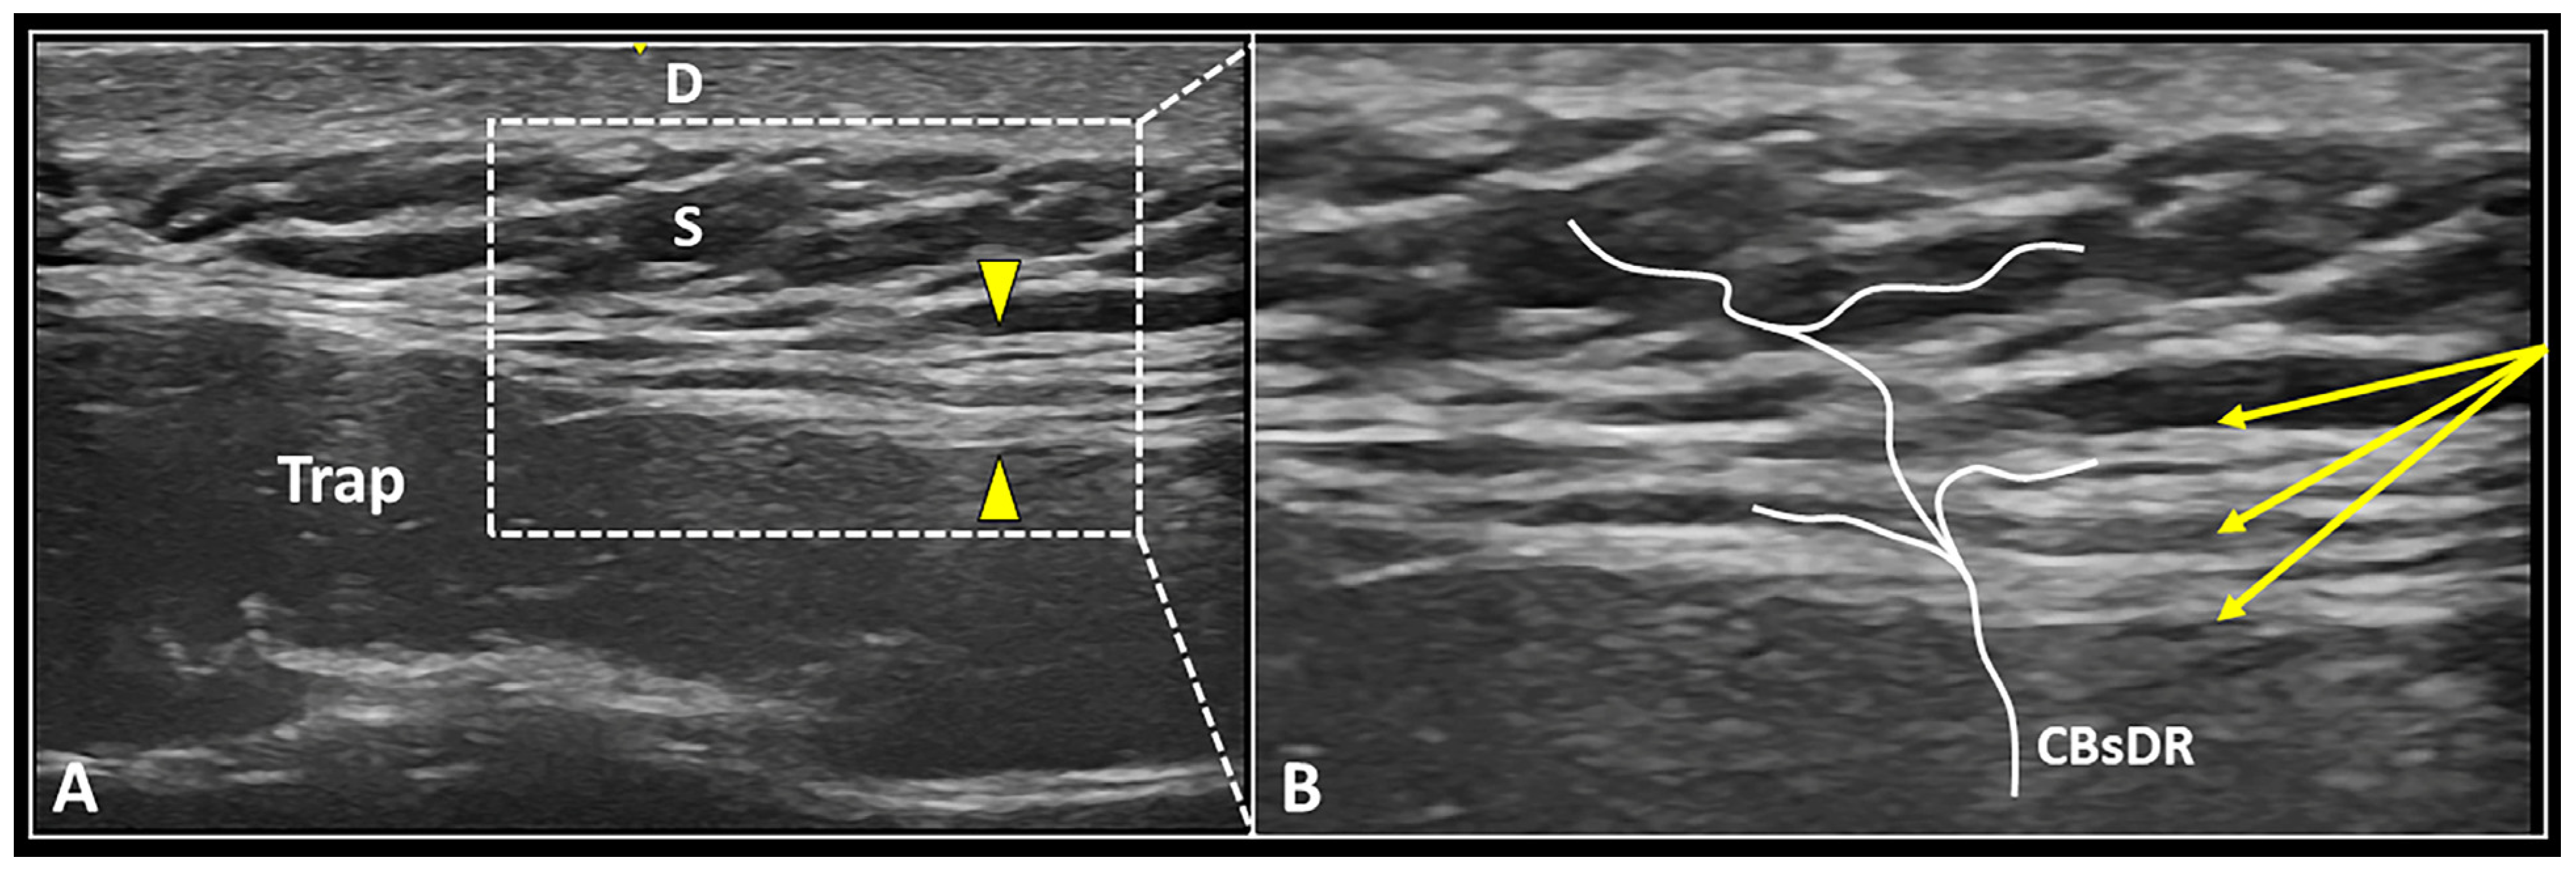

3.4.3. Fascial Hydro-Dissection

- Ricci, V.; Ricci, C.; Mezian, K.; Naňka, O.; Özçakar, L. Trapezius muscle and the cutaneous branches of spinal nerves: Sonographic/anatomic discussion on myofascial pain and superficial injections. Pain Med. 2022, pnac125. [Google Scholar] [CrossRef]

| Deep Fascia/CBsDR | Fascial hydro-dissection | Seeding technique to optimize layer-by-layer dissection |